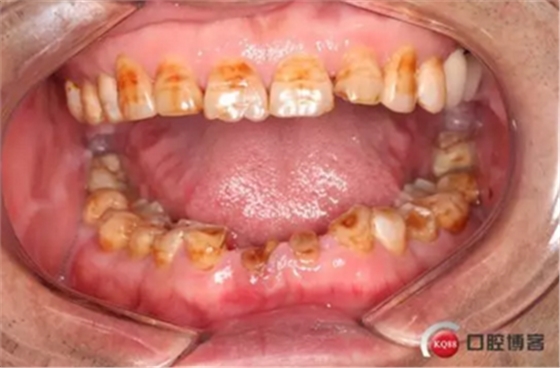

患者,男性,47歲,全身情況良好,無手術(shù)禁忌,口內(nèi)因下前牙缺損松動(dòng)不美觀來院。初診檢查時(shí)發(fā)現(xiàn)患者前牙深覆合,下頜32、42缺失。31、41松動(dòng)二度,切緣磨耗嚴(yán)重,可探及髓腔,無保留價(jià)值。X-RAY檢查顯示:下頜前牙區(qū)寬度狹窄,咬合空間不足,無法行常規(guī)種植修復(fù).

下圖是術(shù)前資料